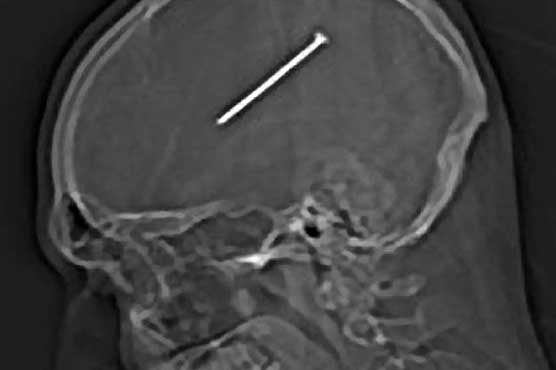

Summary Doctors in the US have removed a three-inch nail from a man's brain.

Dante Autullo remained conscious after the self-inflicted injury and initially believed he had only brushed his nail gun against his head.The 32-year-old, who is recovering in hospital, even continued doing handiwork around his Chicago home for the rest of the day and chatted to his family.But he was taken to hospital the following afternoon after waking up from a nap feeling ill.An X-ray revealed the nail lodged in his brain – but Mr Autullo was still well enough to post an image of the scan on Facebook during an ambulance ride between hospitals.Doctors explained the nail had barely missed the portion of the brain that controls motor function, meaning he was able to carry on with his day.Although there are pain-sensitive nerves on a persons skull, there are none in the brain itself.Following the surgery on Friday, Mr Autullos 33-year-old wife Gail Glaenzer, with whom he has four children, said: He feels good. He moved all his limbs, hes talking normal, he remembers everything.Its amazing, a miracle.